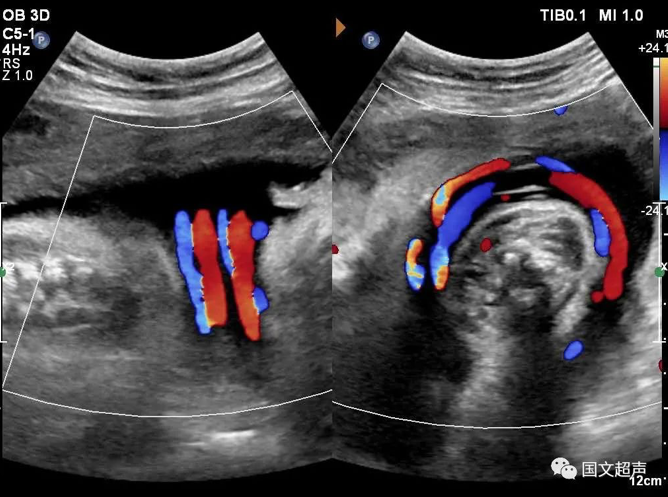

四.關于臍帶繞頸

臍帶有補償性伸展,纏繞松弛對胎兒影響不大,但如果纏繞過緊可影響胎兒血供,有造成胎心率改變、胎兒缺氧、窒息甚至胎死宮內的風險。

實際上影響胎兒預后的主要因素不在于繞頸的周數,而在于除去繞頸所剩的臍帶長度。如果孕媽媽只繞頸一周但臍帶相對過短,仍可造成不良結局。

臍帶繞頸的孩子很多,但發(fā)生不良結局的確占少數,所以不必過度擔心,只要每天的胎動正常,沒有突然的增多和減少,定期復查即可。